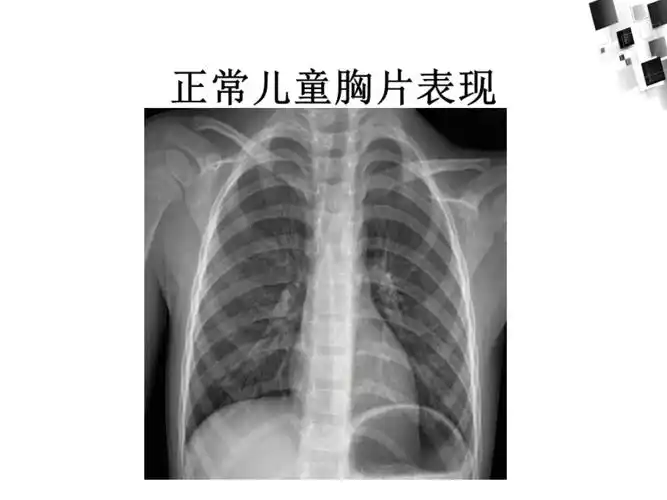

儿童常见肺部感染ppt课件